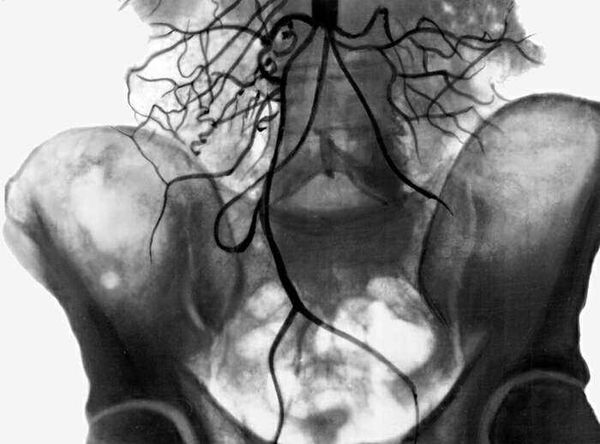

Рентгенография с контрастным веществом предоставляет наглядное изображение сосудистой системы. При подозрении на синдром Лериша применяется транслюмбальная рентгеноконтрастная ангиография перед началом лечения.

Преимуществом этого метода является возможность визуализации не только аорты, но и соседних сосудов. Аортография помогает определить место поражения, его степень и протяженность.